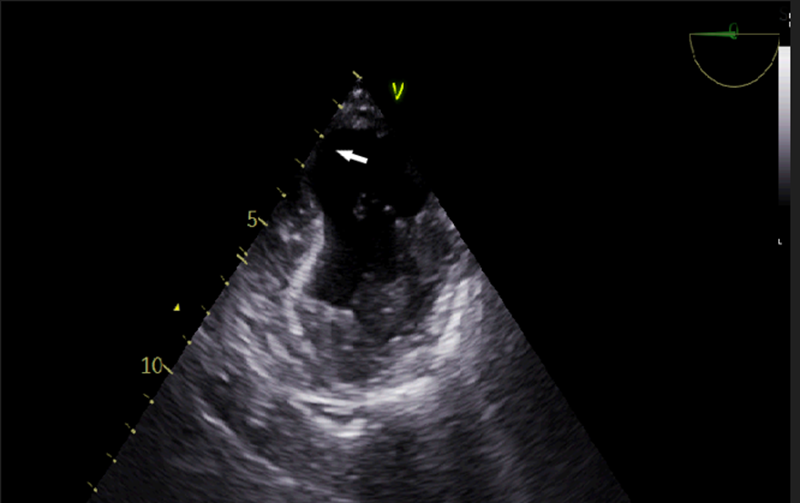

Figure-5a: TG basal LV SAX view, 2D- TEE imaging shows an inferior- posterior wall LV aneurysm (white arrow) with wall thinning and MV in systole.

Figure-5b. Video of TG- basal LV SAX view – 2D TEE imaging shows the thin and aneurysmal inferior wall of the LV, most likely due to CAD involving PDA branch of RCA or LCx. In addition, mild to moderate concentric LVH is also confirmed on TG mid papillary view.

TG basal LV SAX- trans gastric basal left ventricle short axis, 2D- 2 -dimensional, CAD- coronary artery disease, PDA- posterior descending artery, RCA- right coronary artery, LCx – left circumflex artery